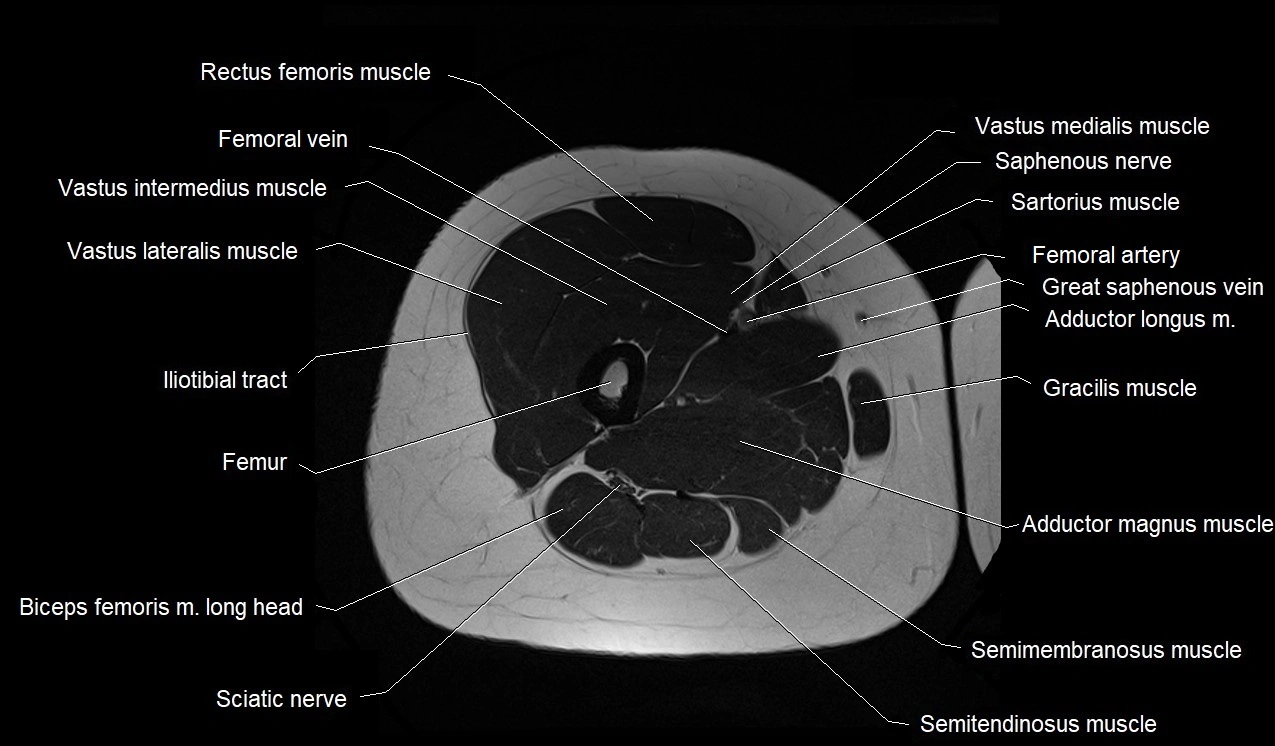

- Adductor longus muscle

- Adductor magnus muscle

- Biceps femoris muscle (Long head)

- Common fibular nerve

- Femoral artery

- Femoral vein

- Femur

- Gracilis muscle

- Iliotibial tract

- Rectus femoris muscle

- Saphenous nerve

- Sartorius muscle

- Semimembranosus muscle

- Semitendinosus muscle

- Vastus intermedius muscle

- Vastus lateralis muscle

- Vastus medialis muscle

- great saphenous vein